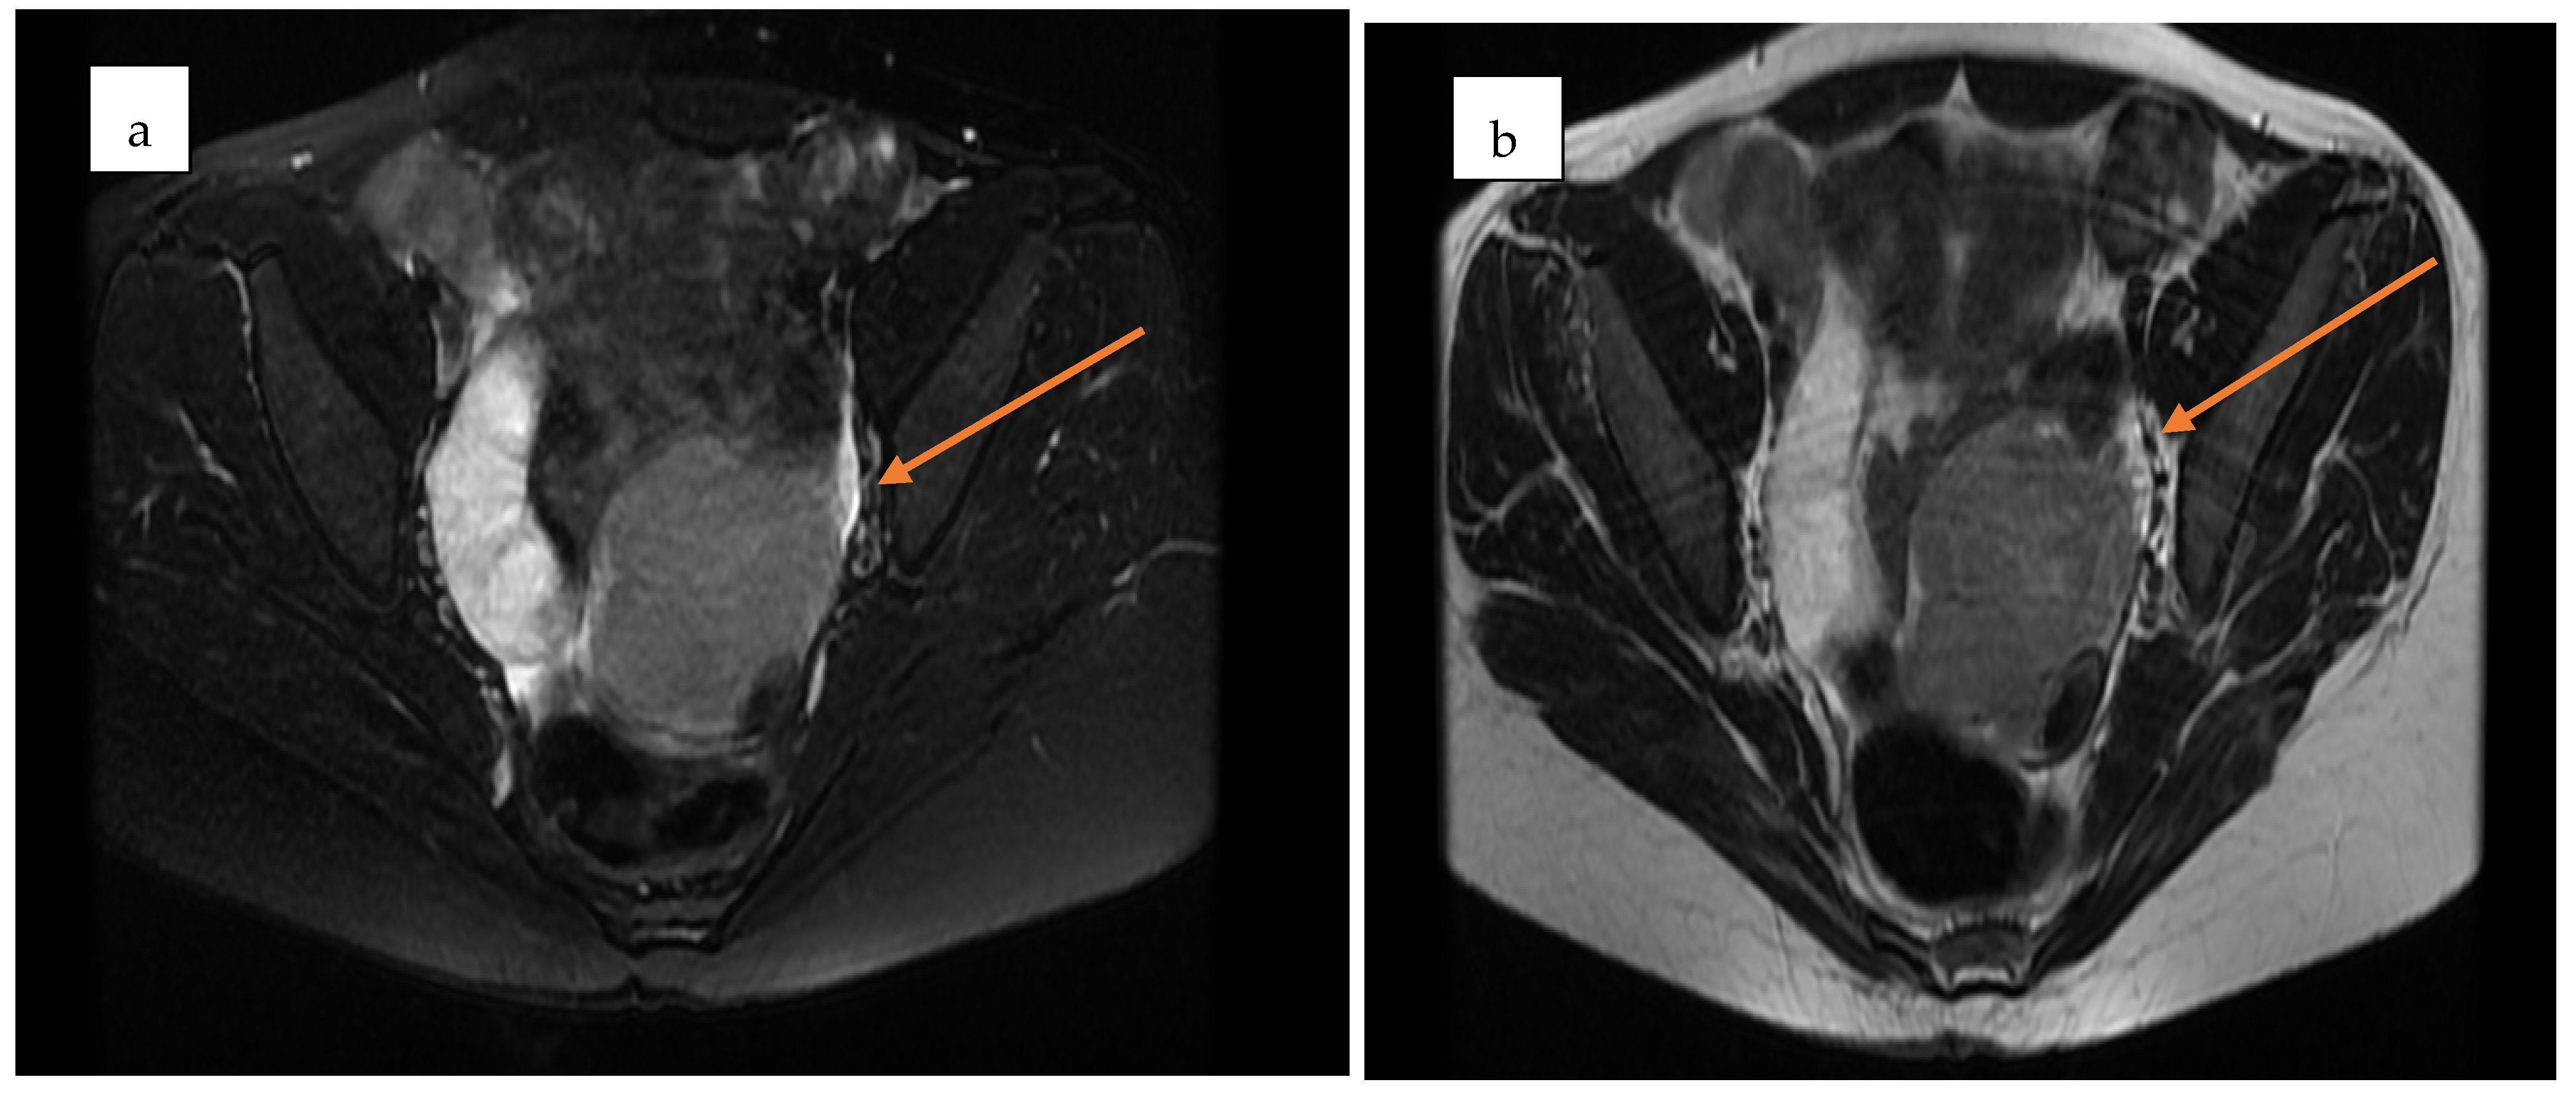

The patient was first evaluated using gynecologic ultrasound, including transvaginal sonography (TVS), which is the first-line diagnostic tool for adnexal masses in clinical practice. Transvaginal sonography (TVS) revealed a complex left adnexal mass with cystic morphology, showing well-defined borders and thin internal septations (Figure 1). Subsequently, magnetic resonance imaging (MRI) was performed as a complementary investigation to provide additional characterization of the lesion and to assist in the differential diagnosis with borderline or malignant ovarian tumors.

Figure 3. Axial pelvic MRI of the adnexal mass in the pouch of Douglas. (a) Pre-contrast T2-weighted image showing a well-encapsulated, septated mass with mixed cystic–solid components (yellow arrow). (b) Post-contrast image demonstrating enhancement of the solid nodular component, consistent with vascularization (yellow arrow).